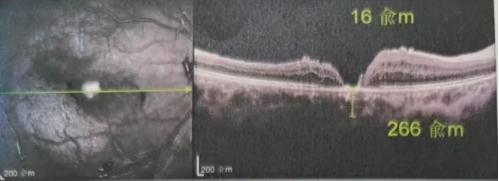

最讓吳爺爺難以置信的是:術(shù)后只需保持平躺24小時(shí)!第二天復(fù)查時(shí),眼底鏡及OCT檢查清晰顯示——那個(gè)折磨了他大半年的大裂孔,竟然閉合了!且吳爺爺?shù)挠已垡暳τ辛嗣黠@的改善,術(shù)后3天已經(jīng)可以看到 0.15。

更為關(guān)鍵的是,患者術(shù)后無需再忍受長時(shí)間的俯臥煎熬,僅需平躺24 小時(shí),裂孔就能實(shí)現(xiàn)閉合,大大提升了患者的舒適度,也降低了其他并發(fā)癥的發(fā)生風(fēng)險(xiǎn)。